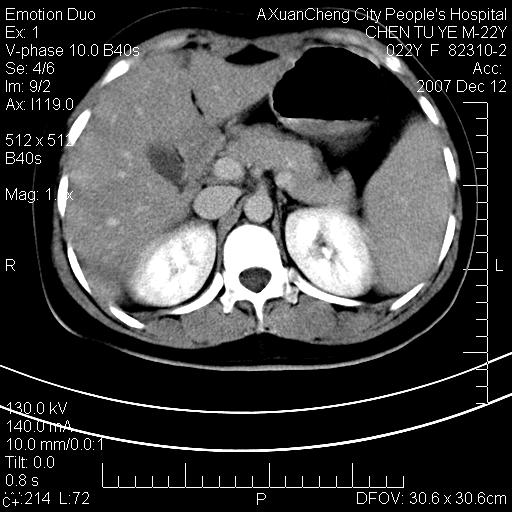

超声提示肝右前叶占位,约2.5cm.

各位战友看看病灶在什么地方,可是右前叶进肝裂部低密度影,平扫ct值约10以下,增强后增高明显

1 脾大,慢性肝损伤. 2 肝脏脂肪侵润.  3 你所指的部位疑点,我没看出有问题.

脂肪肝,脾大

平扫与增强ct值差>10hu的话,应该列为高度疑似病例,我们的职责就是不能放过这样小的病灶.再次b超对比

确定是否同一病灶!运到伪影我坚决反对!